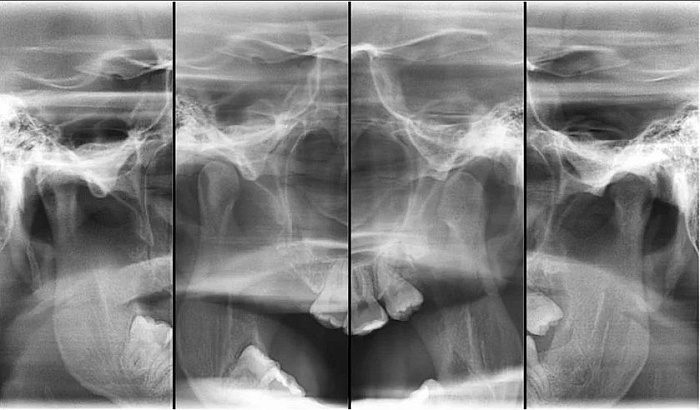

Рентгенография височно-нижнечелюстного сустава – важный метод прицельного исследования височно-нижнечелюстных суставов.

Рентген выполняется в двух проекциях.